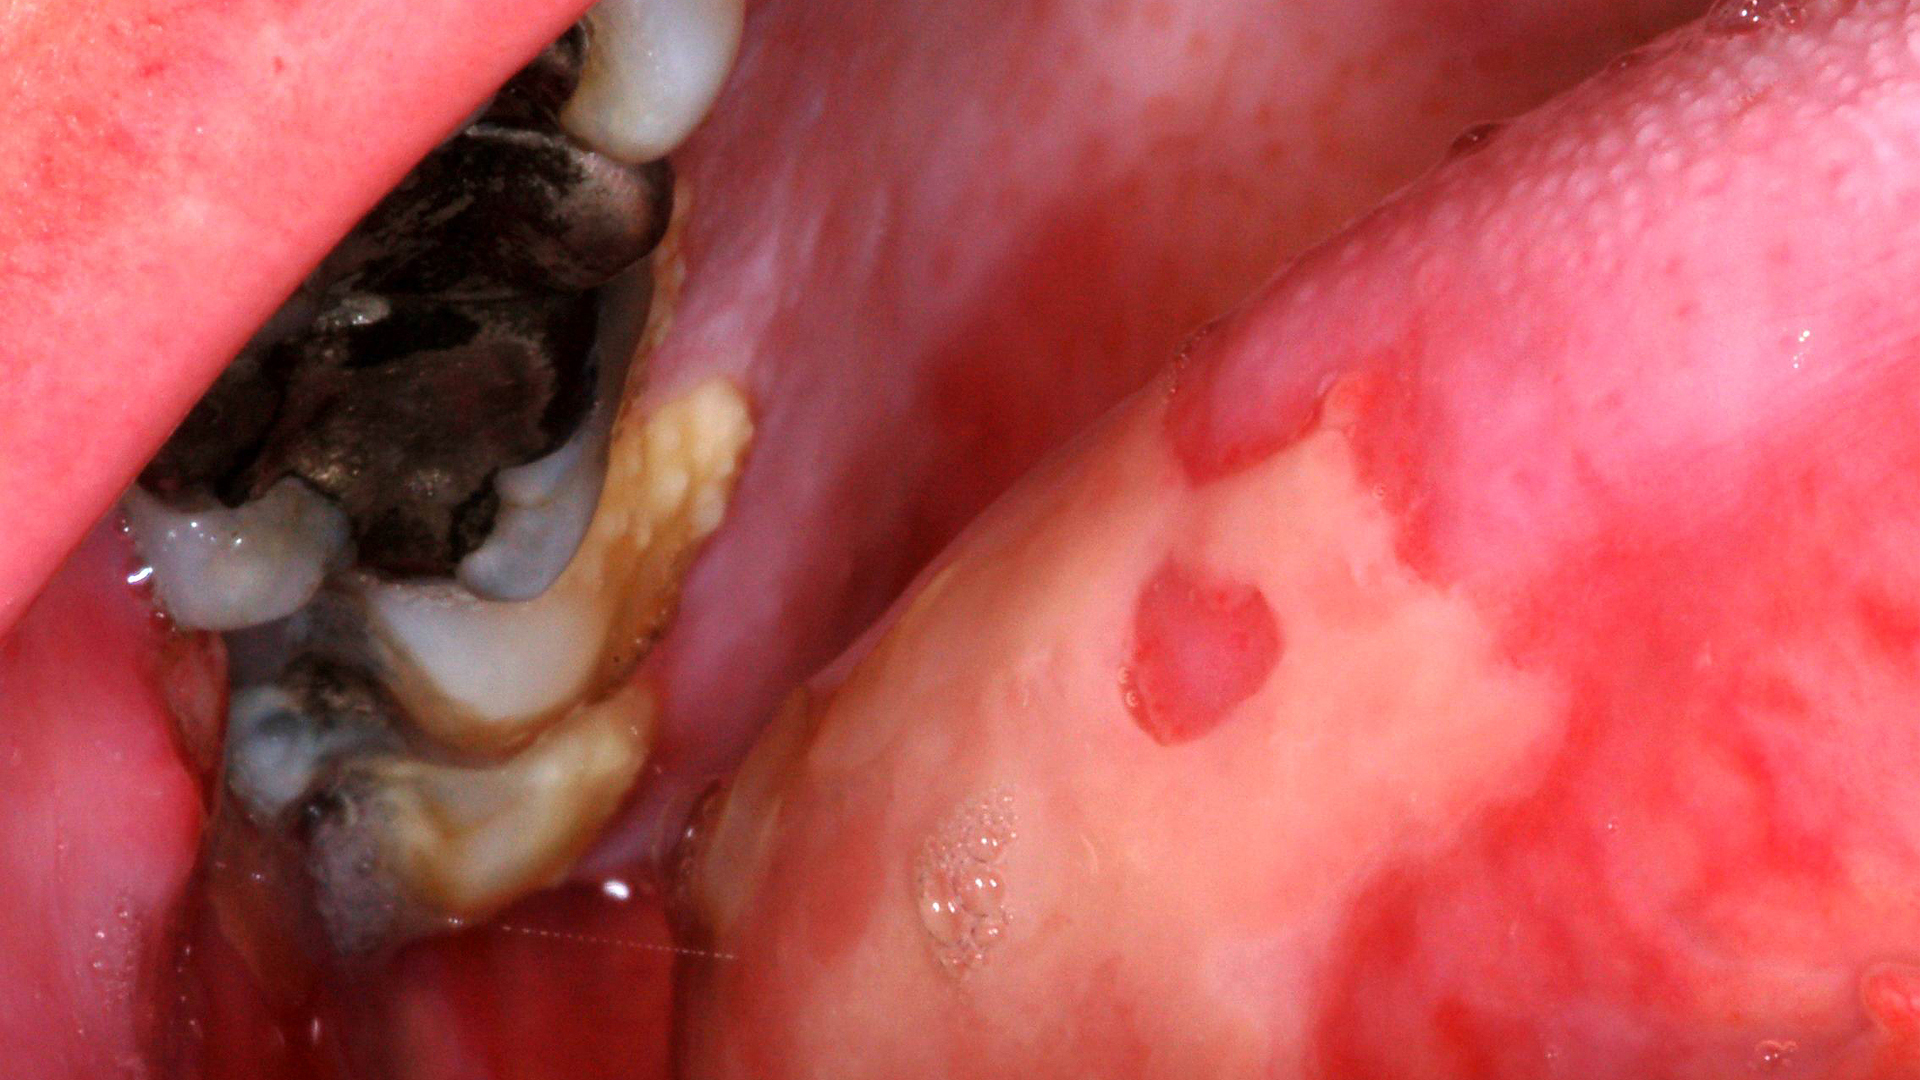

- Apply best practices in treating dental caries, including minimally invasive dentistry.

- Explore contemporary restorative techniques and materials suited for pediatric dentistry.